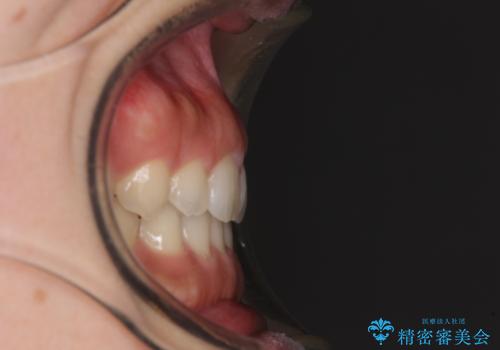

気になる隙間の再矯正 前歯をインビザライン・ライトで改善

- 後戻りによる上下前歯の隙間を気にして来院された患者様です。

歯列不正はそれほど大きくなかったため、インビザライン・ライトを用いて矯正治療を行うこととしました。

無理のないペースで治療を進め、9ヶ月で終えることができました。